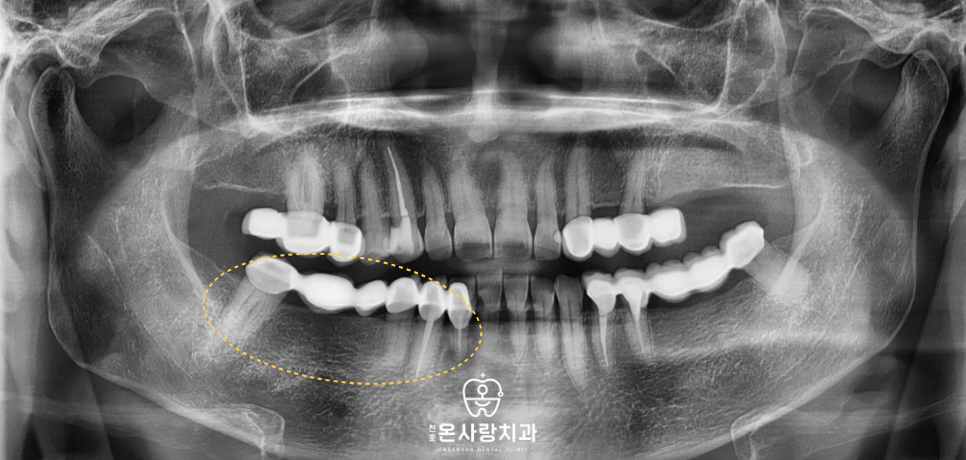

천호온사랑치과를 방문하신 환자분 역시

하악 우측 부위의 모든 치아가

브릿지로 길게 연결되어 있는 상태였습니다.

평소 식사를 할 때 전반적으로

치아에 힘이 실리지 않고

어딘가 모르게 불편함이

지속된다는 점을 호소하셨습니다.

의료진이 정밀한 진단을 통해 살펴본 결과

하악 우측 치아가 하나로 묶여 있는

브릿지 상태였으며 중간에는 2개 치아가

없는 자리를 보철물이 대신하고 있었습니다.

문제는 브릿지를 지탱하고 있는

기둥 치아들의 상태가

제각각이었다는 점입니다.

어떤 치아는 여전히 튼튼했지만

어떤 치아는 내부 손상이 진행되어

더 이상 기둥 역할을 수행하기

어려운 상황이었습니다.